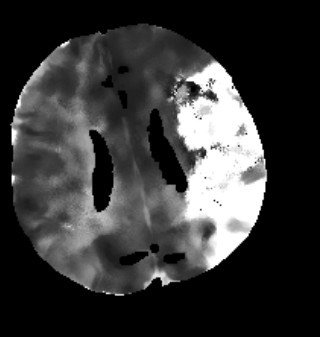

Furthermore mRay is capable of performing image processing tasks such as finding, visualizing and quantifying anomalies in tissue. In particular the image analysis module mRay VEOcore may be used to perform an automated processing of brain images from imaging modalities such as CT, CT-Perfusion, or MRI including a Diffusion Weighted Imaging (DWI) Module. As a result, changes in contrast over time are visualized as colored perfusion maps, including flow related parameters and tissue blood volume quantification.

The perfusion analysis of brain imaging data visualizes and quantifies tissue that is less supplied with blood (penumbra), oxygen deprived tissue caused by obstructed blood flow (core tissue) and the mismatch ratio between the two. The calculated values can be used to support decision making based on an assessment of the extent of tissue damage.

16.1. Overview

VEOcore is a fully automated image processing tool to calculate quantitative measures of affected brain tissue and healthy tissue. Therefore, this manual covers the instructions on how to interpret the results. It’s an extension the mRay Server application and the results can be viewed inside the mRay Client. Furthermore processed results can be automatically forwarded to the PACS.